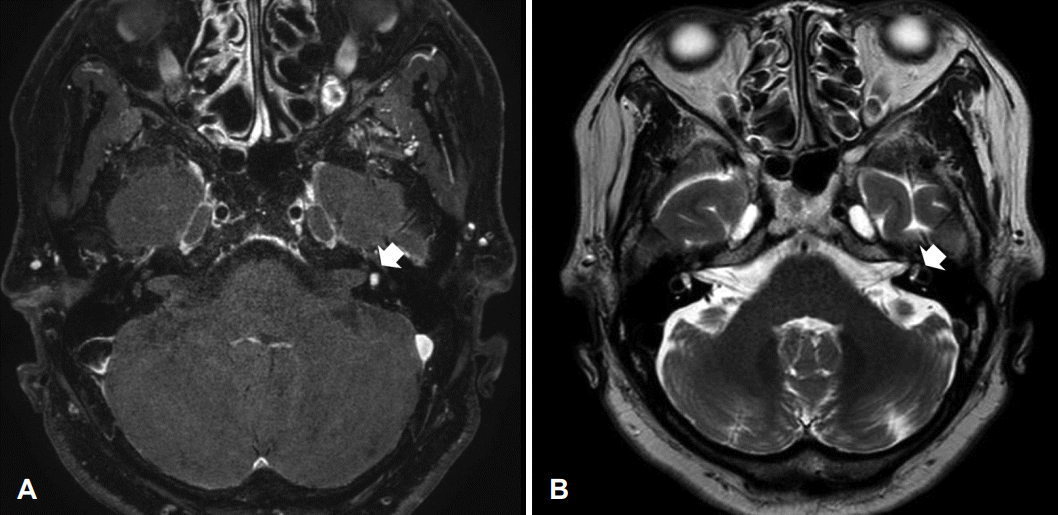

45세 여자 환자가 우측 귀 이명, 이충만감, 청력 저하 증상 발생하여 외래 방문하였다. 초진 때 시행한 신체검사에서 양측 고막은 정상 소견, 순음청력검사에서 우측 농, 좌측 8 dB을 보였다. 최대어음명료도에서 우측은 0%, 좌측은 100%의 소견을 보였고 고막 임피던스 검사상에서 양측 정상이었다. 비디오 두부충동검사에서 우측이 좌측에 비해 기능이 떨어진 것이 확인되었으며 시선재고정 단속운동관찰되었다. 전정 유발 근전위 검사에서 우측이 58% 정도 진폭이 감소된 소견이 관찰되었다(Fig. 6). 측두골 자기공명영상 검사에서 우측 전정 내에 T1 강조영상에서 고신호강도로 관찰되며 T2 강조 영상에서는 충만 결손 소견이 관찰되는 0.5×0.3 cm 정도 크기의 미로내 종괴가 관찰되었다(Fig. 7).

미로내 신경초종에 대한 진단을 위해서는 조영제를 이용한 측두골 자기공명영상이 필요하다[5]. 종양은 일반적으로 T1 강조영상에서는 조영 증강을 보이며 T2 강조영상에서는 음영 결손을 보이는 양상을 보인다[6].